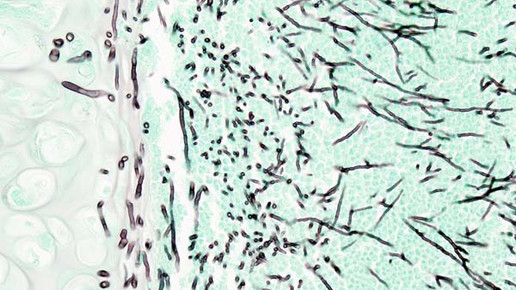

Caspofungin ist ein Glukansynthesehemmer mit breitem Wirkspektrum gegen Aspergillus- und Candida-Arten. Das Echinocandin unterbindet die Synthese von Beta-(1,3)-D-Glukan, dem Hauptbestandteil der Zellwand von Fadenpilzen und Hefen. Die Apikalenden und Verzweigungspunkte der Hyphen sind die Orte der Zellteilung und des Zellwachstums der Pilze. Diese sterben durch die Gabe von Caspofungin ab. Zellwände von Säugetieren enthalten den Bestandteil nicht und werden somit nicht angegriffen.